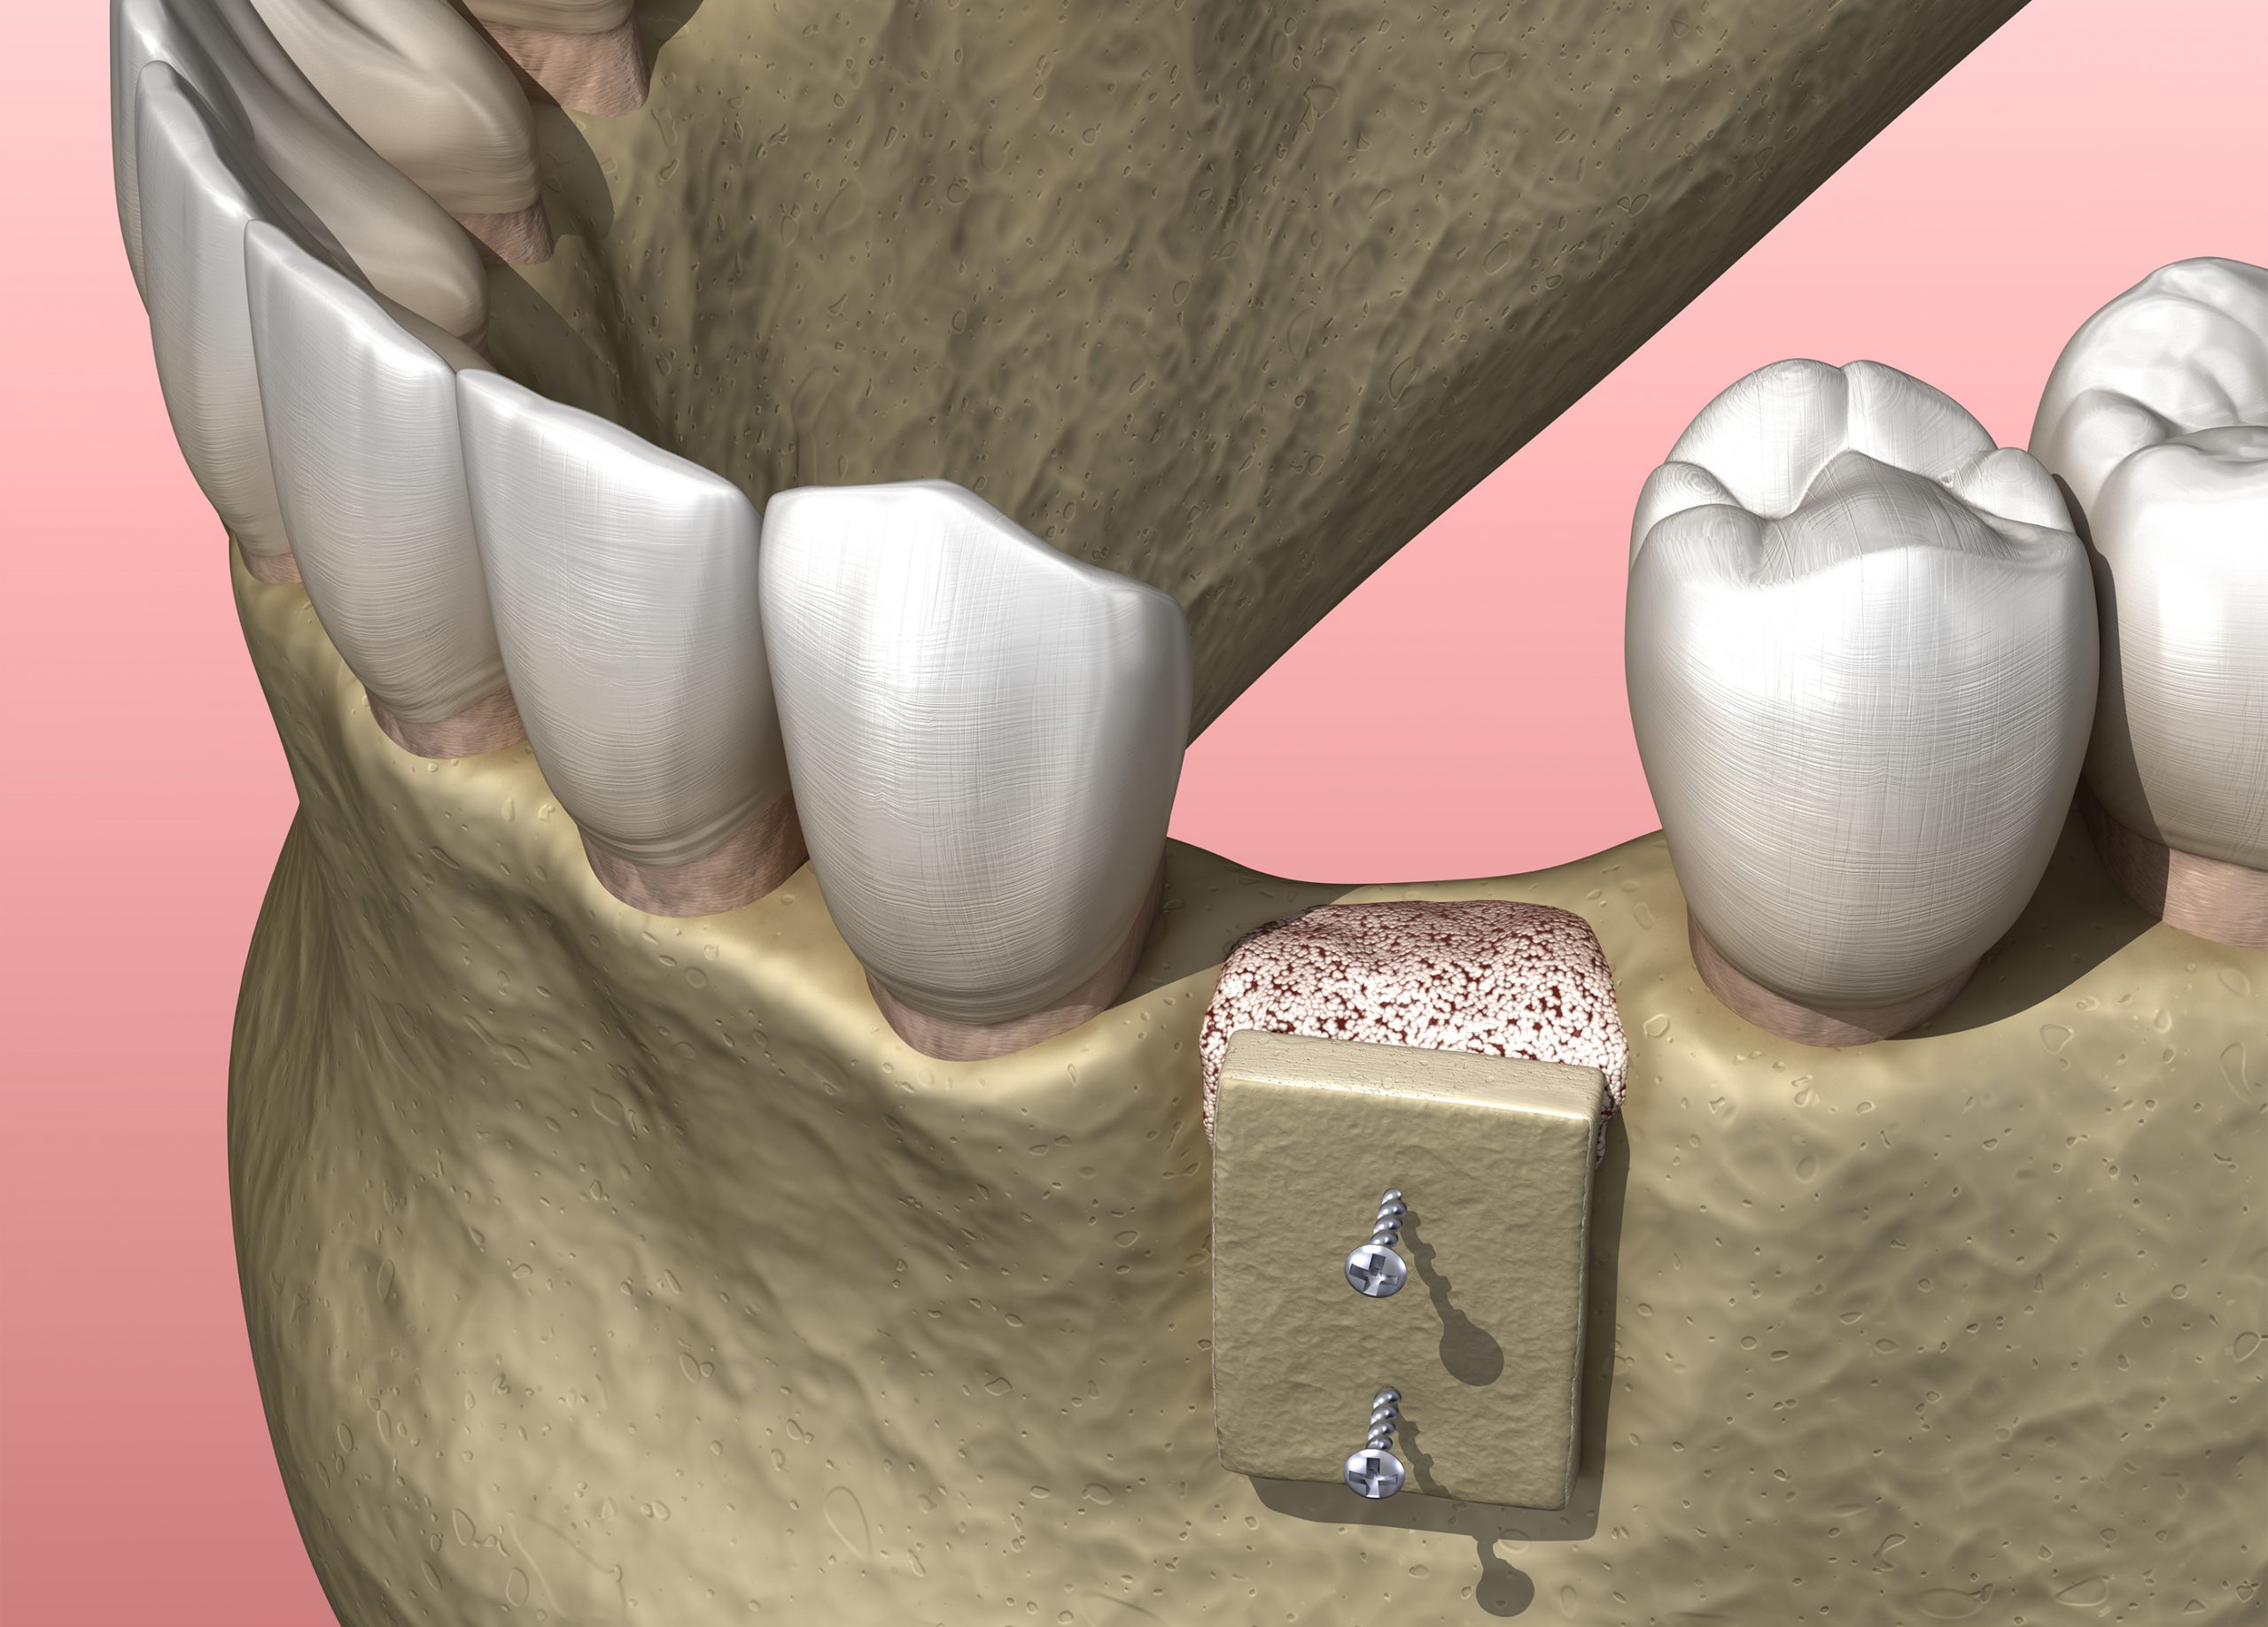

転倒などで顔面に強い衝撃を受けると、歯だけでなく顎の骨まで折れることも珍しくありません。重症例では折れた顎の骨が大きくズレたり、広範囲に顎骨を失ったりします。いずれもすぐにインプラント治療を開始するのは不可能です。まずは、顎の骨の治療を優先します。ズレた骨は整復処置を施し、欠損した部分は骨移植を実施します。そうして顎の骨の状態が良好になったら、インプラント治療を開始します。外傷後の骨移植を行うようなケースでは、6~12ヶ月程度、治癒期間を設ける必要があります。

外傷によって失った骨は、GBR法やブロック骨移植などで補います。GBRは通常のインプラント治療でもよく行われる治療法で、骨が欠損した部位に患者さまご自身の骨(自家骨)や人工骨を移植して再生をはかります。ブロック骨移植は、欠損が比較的大きい場合に適応される外科処置で、患者さまご自身の骨をブロック状で削り出し、欠損部に移植する方法です。移植骨は下顎の親知らずや前歯の周囲から削り出します。

外傷によって失った骨は、GBR法やブロック骨移植などで補います。GBRは通常のインプラント治療でもよく行われる治療法で、骨が欠損した部位に患者さまご自身の骨(自家骨)や人工骨を移植して再生をはかります。ブロック骨移植は、欠損が比較的大きい場合に適応される外科処置で、患者さまご自身の骨をブロック状で削り出し、欠損部に移植する方法です。移植骨は下顎の親知らずや前歯の周囲から削り出します。